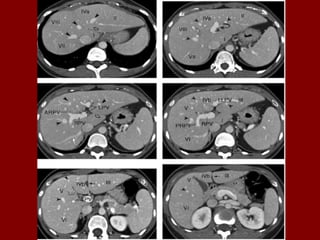

Ac Colo ascendente AP Nível de ar fluido do estômago Ao Aorta Az Veia ázigo CA Tronco celíaco cc Cartilagem costa! CD Dueto cístico CHA Artéria hepática comum CHD Dueto comum CL Lobo caudado fígado D Diafragma DBM Músculos profundos do De Colo descendente D2 Parte descendente do duodeno D3 Parte horizontal do duodeno E Esôfago FL Ligamento falciforme GB Vesícula biliar HA Artéria hepática Hz Veia IMV Divisão da veia mesentérica inf. A IVC Veia cava inferior LC Ramo esq. do diafragma LG Glândula supra-renal esq. LHV Veia hepática esquerda LIL Lobo inf. Esq. do pulmão LRV Veia renal esquerda LK Rim esquerdo LU Ureter esquerdo LL Lobo esquerdo do fígado MHV Veia hepática média P Pâncreas PA Antro pilórico do estômago

Ac Colo ascendente AP Nível de ar fluido do estômago Ao Aorta Az Veia ázigo CA Tronco celíaco cc Cartilagem costa! CD Dueto cístico CHA Artéria hepática comum CHD Dueto comum CL Lobo caudado fígado D Diafragma DBM Músculos profundos do De Colo descendente D2 Parte descendente do duodeno D3 Parte horizontal do duodeno E Esôfago FL Ligamento falciforme GB Vesícula biliar HA Artéria hepática Hz Veia IMV Divisão da veia mesentérica inf. IVC Veia cava inferior B LC Ramo esq. do diafragma LG Glândula supra-renal esq. LHV Veia hepática esquerda LIL Lobo inf. Esq. do pulmão LRV Veia renal esquerda LK Rim esquerdo LU Ureter esquerdo LL Lobo esquerdo do fígado MHV Veia hepática média P Pâncreas PA Antro pilórico do estômago

Ac Colo ascendente AP Nível de ar fluido do estômago Ao Aorta Az Veia ázigo CA Tronco celíaco cc Cartilagem costa! CD Ducto cístico CHA Artéria hepática comum CHD Ducto comum CL Lobo caudado fígado D Diafragma DBM Músculos para vertebrais De Colo descendente D2 Parte descendente do duodeno D3 Parte horizontal do duodeno E Esôfago FL Ligamento falciforme GB Vesícula biliar HA Artéria hepática Hz Veia IMV Divisão da veia mesentérica inf. C IVC Veia cava inferior LC Ramo esq. do diafragma LG Glândula supra-renal esq. LHV Veia hepática esquerda LIL Lobo inf. Esq. do pulmão LRV Veia renal esquerda LK Rim esquerdo LU Ureter esquerdo LL Lobo esquerdo do fígado MHV Veia hepática média P Pâncreas PA Antro pilórico do estômago

Ac Colo ascendente AP Nível de ar fluido do estômago Ao Aorta Az Veia ázigo CA Tronco celíaco cc Cartilagem costa! CD Dueto cístico CHA Artéria hepática comum CHD Dueto comum CL Lobo caudado fígado D Diafragma DBM Músculos profundos do De Colo descendente D2 Parte descendente do duodeno D3 Parte horizontal do duodeno E Esôfago FL Ligamento falciforme GB Vesícula biliar HA Artéria hepática Hz Veia IMV Divisão da veia mesentérica inf. D IVC Veia cava inferior LC Ramo esq. do diafragma LG Glândula supra-renal esq. LHV Veia hepática esquerda LIL Lobo inf. Esq. do pulmão LRV Veia renal esquerda LK Rim esquerdo LU Ureter esquerdo LL Lobo esquerdo do fígado MHV Veia hepática média P Pâncreas PA Antro pilórico do estômago

PB Corpo do pâncreas PC Confluência portal PF Gordura perirrenal PH Cabeça do pâncreas PS Músculo psoas PT Cauda do pâncreas PU Processo uncinado do pâncreas PV(R) Ramo direito da veia porta QL Músculo quadrado do lombo R Costela RA Músculo reto do abdome RC Pilar direito do diafragma RF Gordura retroperitoneal RG Glândula supra-renal dir. RHV Veia hepática direita RIL Lobo inf. do pulmão dir. RK Rim direito RL Lobo direito do fígado RP Pelve renal RPV Veia porta RRA Artéria renal direita E RRV Veia renal direita RU Ureter direito S Processo espinhoso SA Artéria esplênica SC Medula espinal Sp Baço SF Flexura esq. do colo St Estômago SI Intestino delgado SV Veia esplênica SMA Artéria mesentérica sup. Tc Coto transverso SMV Veia mesentérica sup. TVP Processo transverso Xp Processo xifóide

PB Corpo do pâncreas PC Confluência portal PF Gordura perirrenal PH Cabeça do pâncreas PS Músculo psoas PT Cauda do pâncreas PU Processo uncinado do pâncreas PV(R) Ramo direito da veia porta QL Músculo quadrado do lombo R Costela RA Músculo reto do abdome RC Pilar direito do diafragma RF Gordura retroperitoneal RG Glândula supra-renal dir. RHV Veia hepática direita RIL Lobo inf. do pulmão dir. RK Rim direito RL Lobo direito do fígado RP Pelve renal RPV Veia porta RRA Artéria renal direita F RRV Veia renal direita RU Ureter direito S Processo espinhoso SA Artéria esplênica SC Medula espinal Sp Baço SF Flexura esq. do colo St Estômago SI Intestino delgado SV Veia esplênica SMA Artéria mesentérica sup. Tc Coto transverso SMV Veia mesentérica sup. TVP Processo transverso Xp Processo xifóide

G H PB Corpo do pâncreas R Costela RP Pelve renal PC Confluência portal RA Músculo reto do abdome RPV Veia porta PF Gordura perirrenal RC Pilar direito do diafragma RRA Artéria renal direita PH Cabeça do pâncreas RF Gordura retroperitoneal RRV Veia renal direita PS Músculo psoas RG Glândula supra-renal dir. RU Ureter direito PT Cauda do pâncreas RHV Veia hepática direita S Processo espinhoso PU Processo uncinado do pâncreas RIL Lobo inf. do pulmão dir. SA Artéria esplênica PV(R) Ramo direito da veia porta RK Rim direito SC Medula espinal QL Músculo quadrado do lombo RL Lobo direito do fígado SF Flexura esq. do colo SI Intestino delgado SV Veia esplênica SMA Artéria mesentérica sup. Tc Coto transverso SMV Veia mesentérica sup. TVP Processo transverso Sp Baço Xp Processo xifóide St Estômago